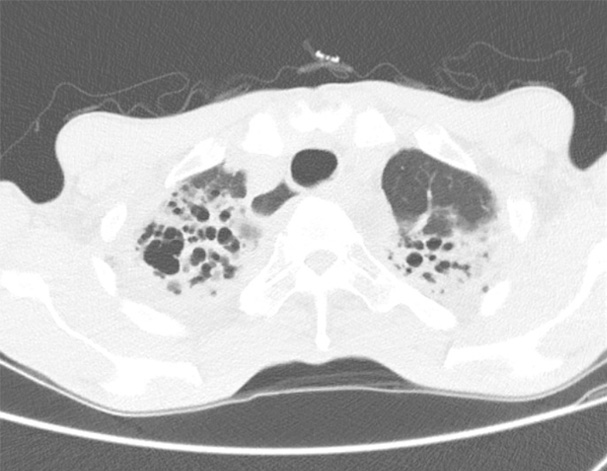

비결핵항산균에 감염된 폐사진